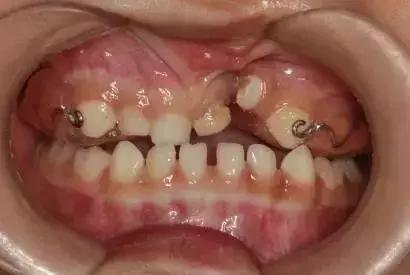

专业地说,儿童乳牙期“地包天”,就是乳下前牙咬合于乳上前牙唇侧,也叫乳前牙反颌。

简单说,就是下面牙齿把上面牙齿款到了,限制了上面牙齿和骨头的发育。